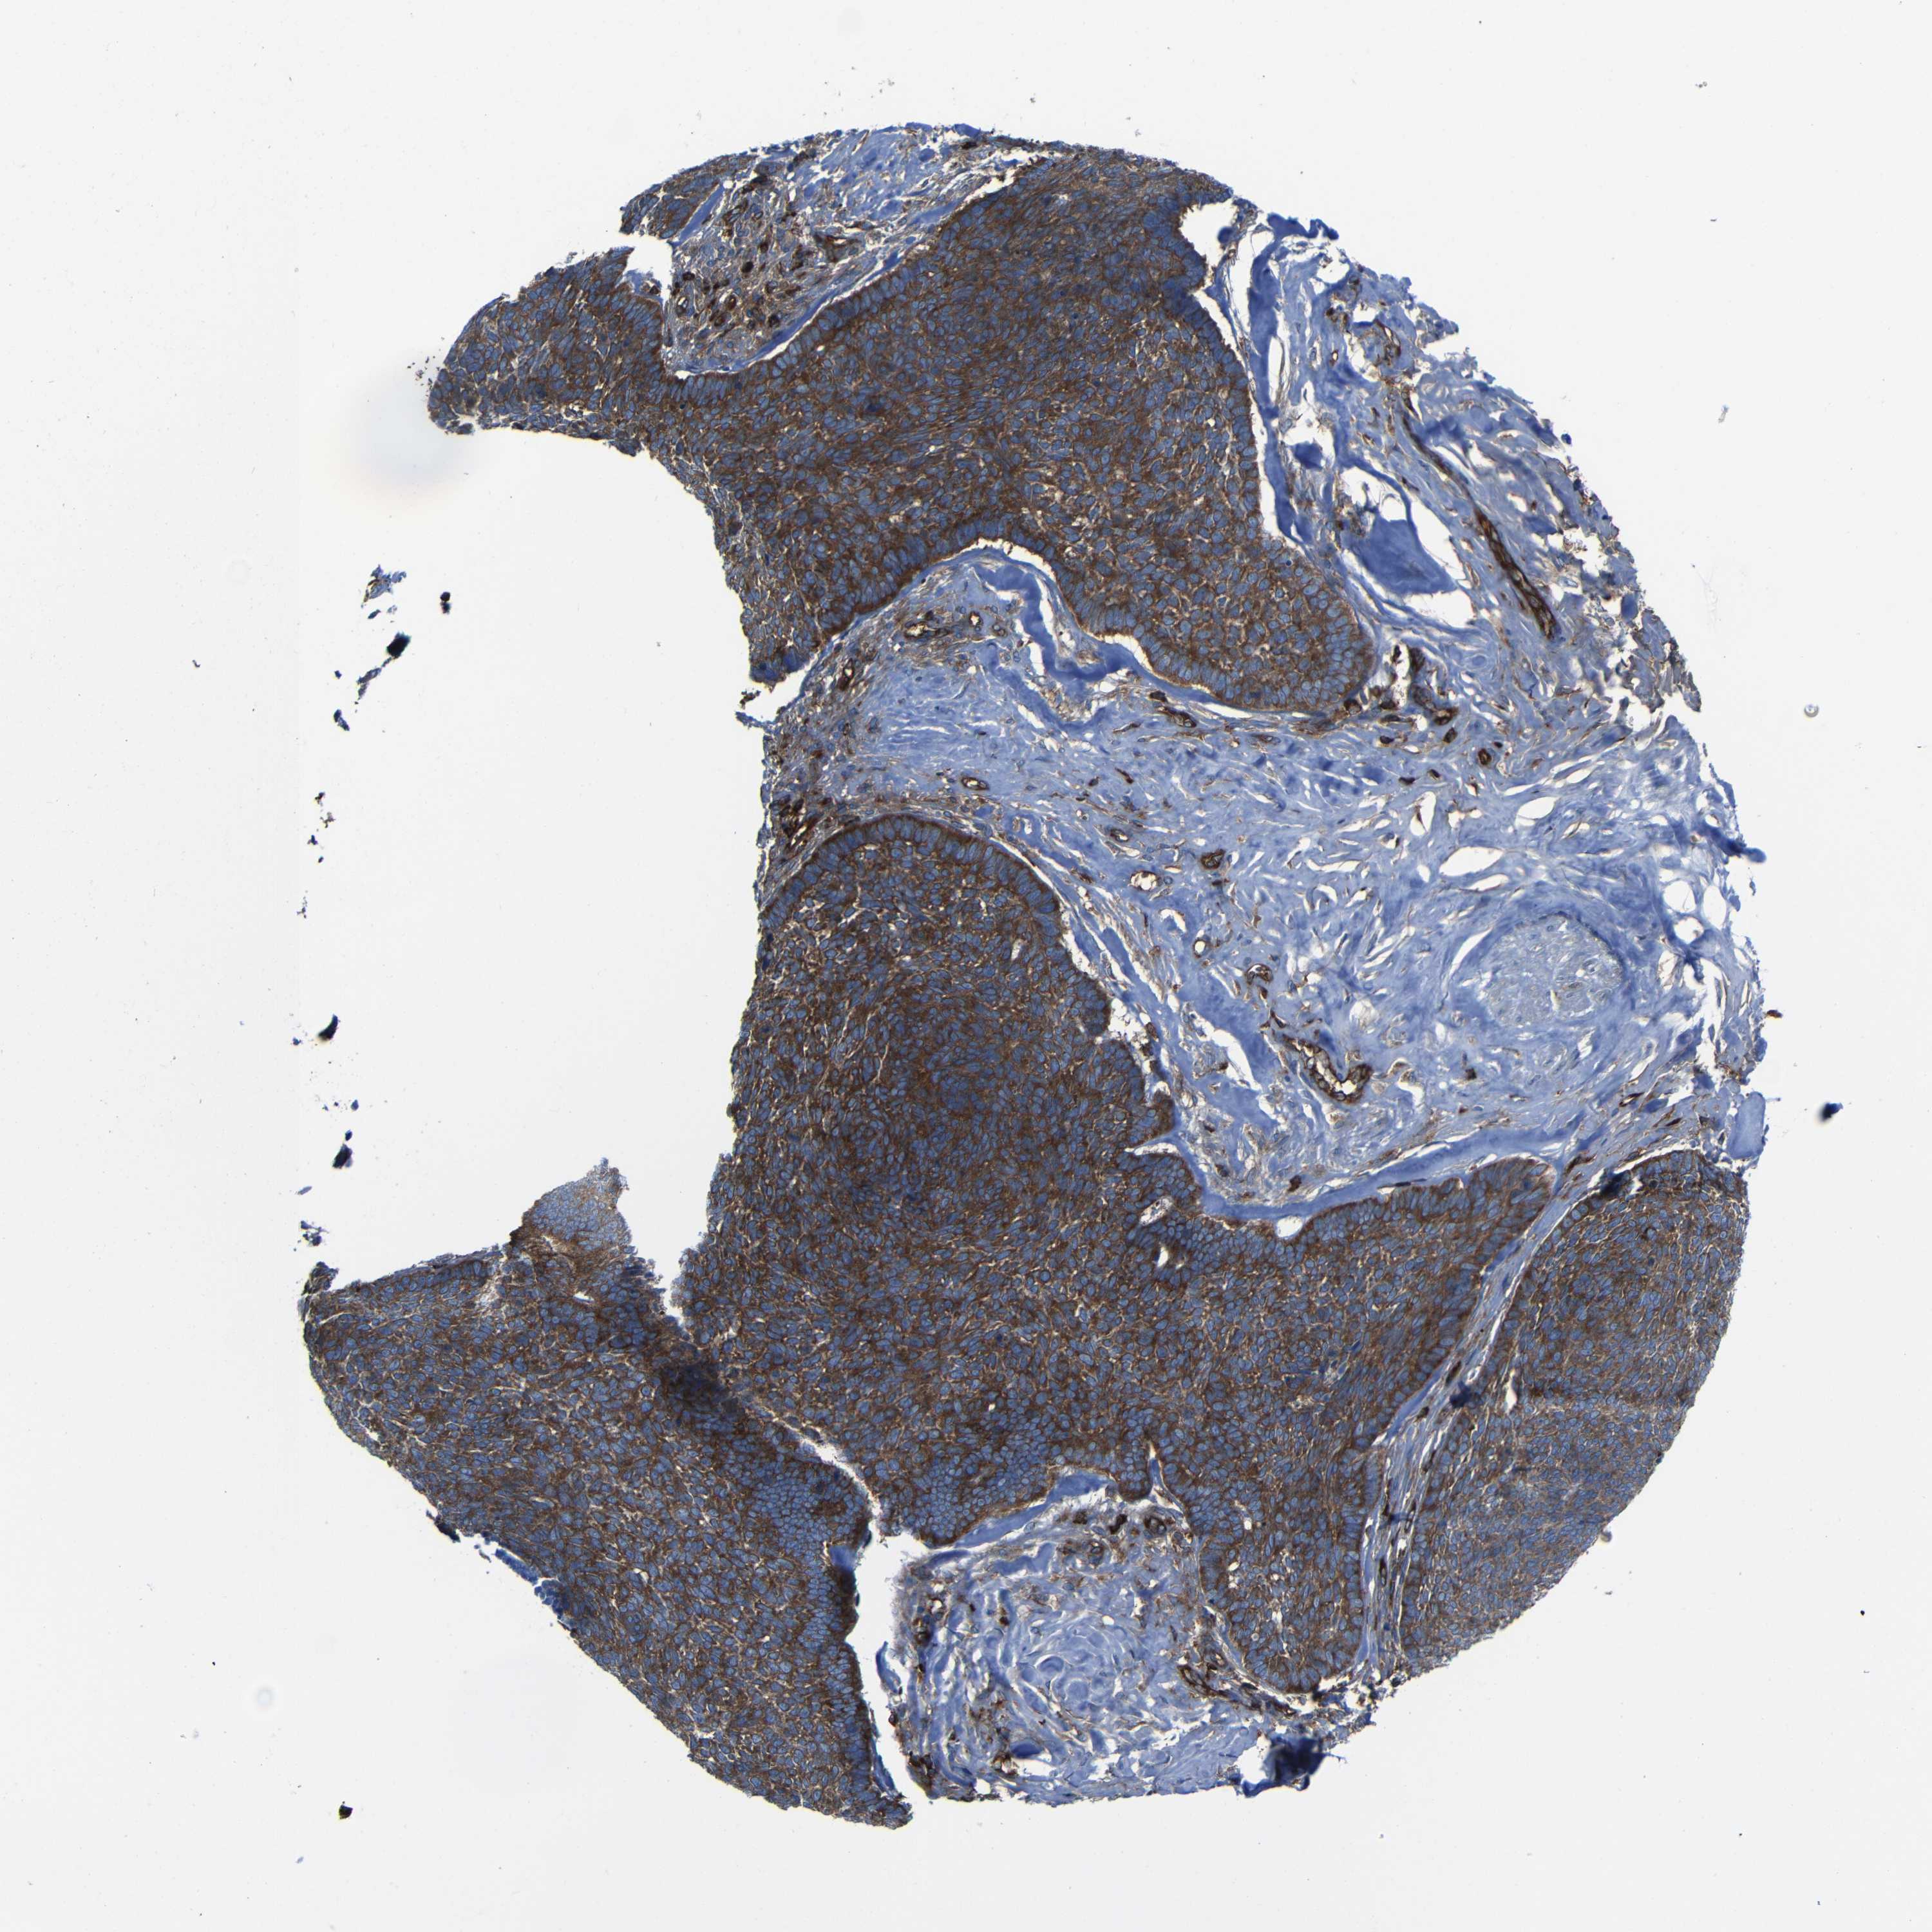

CANCER SKIN CANCER Show tissue menu

Basal cell and squamous cell cancer

SKIN CANCER - Protein expressioni

A mouse-over function shows sample information and annotation data. Click on an image to view it in a full screen mode. Samples can be filtered based on level of antibody staining by selecting one or several of the following categories: high, medium, low and not detected. The assay and annotation is described here.

Each image is clickable and will lead to virtual microscopy that enables deeper exploration of all samples and also displays staining intensity scores, fraction scores and subcellular localization as well as patient and tissue information for each sample.

Antibody CAB009502

Basal cell carcinoma